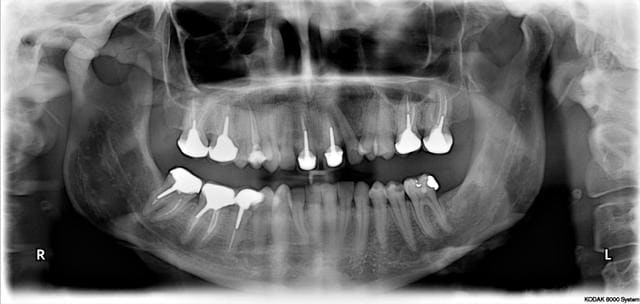

Patiente vue hier pour tout autre chose.

40 ans, bruxomane, aucune symptomatologie.

Porte actuellement une gouttiere maxillaire.

Trauma a 17 ans ayant entrainé la fracture des deux centrales.

Je suis tres intrigué par la difference de hauteur des branches montantes.

curieusement, la branche horizontale paraît plus courte

compensation par croissance du condyle, d'origine paost-traumatique, voire orthondontique

ou plus simplement un mauvais positionnement au moment de la prise du défilé?

Non la pano a été prise correctement.

La patiente n'a pas eu de ttt odf, en bouche il y a un decalage des freins de 4mm, mais les milieux inter incisifs sont centrés.

Sa seule "gene" est une limitation d'ouverture a deux doigts.

Le trauma me semble tardif pour une telle différence, non?

Absence de canine gauche, compensée car sans doute ancienne et surtout 27 sans antagoniste et couronnée de surcroit.

la pano est pas correcte, il suffit de comparer les largeurs MD des molaires et prémolaires inf

Dis nous Pier, comment cela explique la difference de hauteur des condyles?, la difrence de longeur mandibulaire et aussi la diffrence d'épaisseur mandibulaire?

Les branches horizontales et verticales des mandibules n'ont quasiment jamais la même longueur.

Leur apparente superposabilité n'est qu'un leurre du aux références radiologiques qui sont les conduits auditifs externes. Une analyse gnathostatique de Planas en trois dimensions montre les différences. Sachant que tous les os mandibulaires sont soumis durant la croissance à des dissymétries fonctionnelles (mastication unilatérale ou préférentielle : cf Planas comme l'a dit Jeff2).

De plus la croissance de la mandibule est directement sous l'influence des déformations de la base du crâne à la naissance. Déformations souvent visibles directement sur le visage d'un adulte.

Les pentes condyliennes sont aussi très souvent différentes entre la gauche et la droite. Toujours même raisons. L'essentiel est que le patient soit équilibré tel qu'il est !

Une panoramique aussi bonne soit elle n'est que la transposition en deux dimensions d'un élément existant en trois dimension.

La panoramique montre qu'il manque une dent en antagoniste de 27, cela a-t-il provoqué des répercussion?

La panoramique montre des modifications des structures osseuses, sont elles des adaptations ou des perturbations.

A propos de ce que permet la pano, l'auteur relève ceci à propos de l'atm :

-hypoplasie du condyle

-hypertrophie du condyle

-anomalies de développement

-asymétries de développement

-variation de l'angle du condyle.

Avec les limites de la technique : déformation secteur antérieur, déformation verticale (ne pas tenir compte des asymétries des branches montantes en-dessous de 6%), déformation de la région des atm pcq perte d'orthogonalité et changement d'épaisseur de coupe.